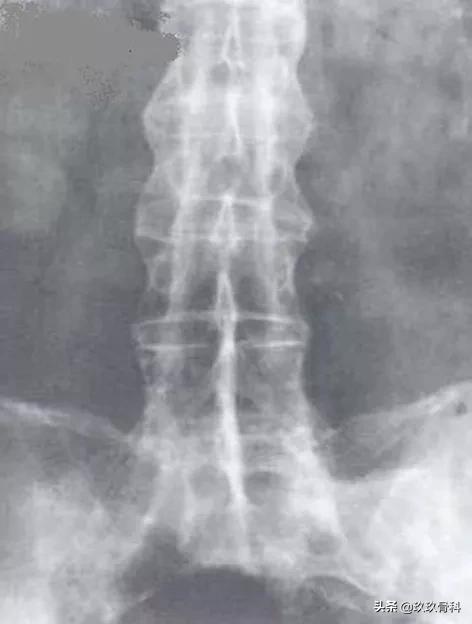

强直性脊柱炎(Ⅰ级)

图注:椎体方形,骨质疏松,椎小关节间隙消失,强直,椎旁韧带(前后纵及棘间韧带)骨化,呈典型“竹节样”改变。双侧骶髂关节骨性强直,髂腰韧带骨化。